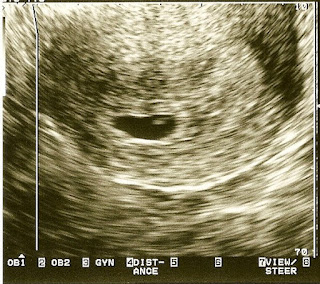

One of the nice things about my health problems is that it has resulted in a lot of ultrasound pictures tracking the baby's growth, which has been fun to see.

Here she is at approximately 6 weeks (at the fertility clinic):